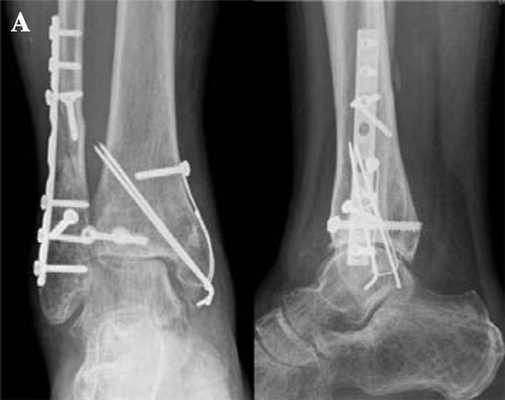

В последние годы возможности эндопротезирования расширились, операционные методы лечения остеоартроза стали более прогрессивными. Хирурги-ортопеды прибегают к сопроводительным мерам для улучшенной фиксации протеза. В их числе - коррекция опоры, пластика большеберцовой коллатеральной и наружной связок, рефиксация и подтяжка связок, другие операции, улучшающие стабильность в положении стоя, при максимальной нагрузке на протез. Подобные мероприятия проводят за несколько месяцев до эндопротезирования.

Чтобы протез прослужил максимально долго, на подготовительном этапе хирурги устраняют деформации, полученные вследствие аварий и травм. Чем больше отклонений оси от нормы, тем быстрее наступит износ протеза. Поэтому врачи стремятся правильно выставить задний отдел стопы и избавиться от деформаций.